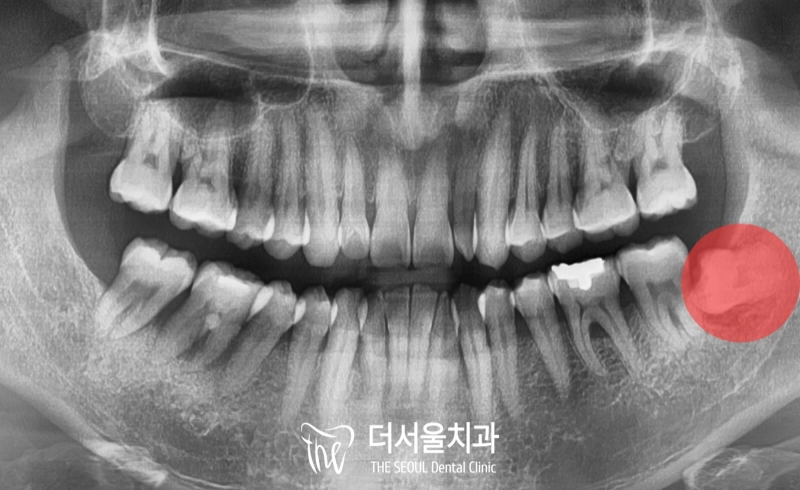

복정동 치과 사랑니 발치 노르웨이 외국인도 소개 받아온 극악의 난이도 (해외 진출 가능?)

안녕하십니까, 복정동 더서울 치과 쌍둥이 박현성 원장입니다. 오늘 소개해드릴 임상 증례는 노르웨이에서 오셨던 환자로 한국에 놀러온 겸 의료 기술이 […]